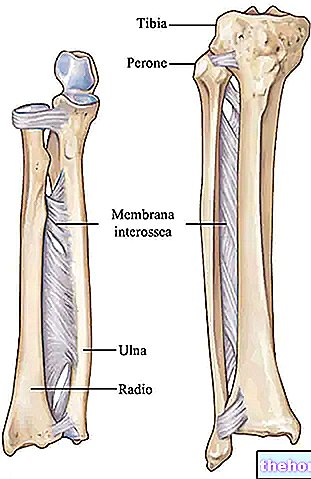

Структура и анатомия синдесмоза: научные иллюстрации